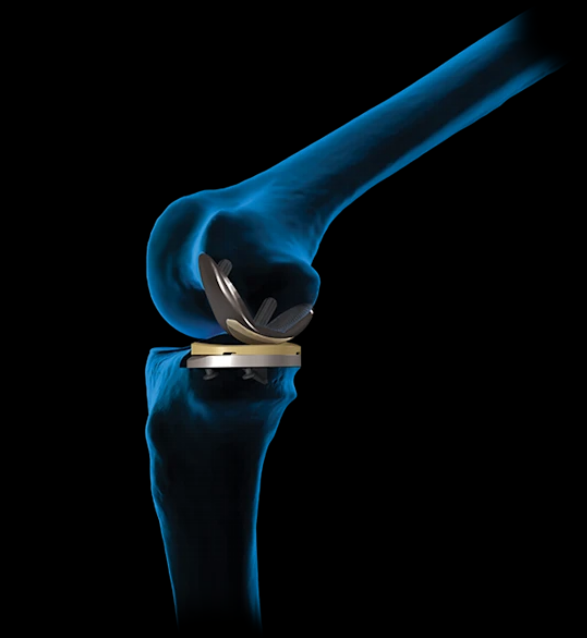

Arthrex Products

Arthrex’s innovative spirit has pioneered the field of arthroscopy and sports medicine and led to the development of more than 1,000 innovative products and procedures each year. Focused on patient safety and clinical outcomes, Arthrex is also leading the way in the fields of orthobiologics and arthroplasty, and is making breakthroughs in the treatment of arthritis. Additionally, we are developing new technologies with potential multispecialty applications.

Knee

Knee Arthroplasty